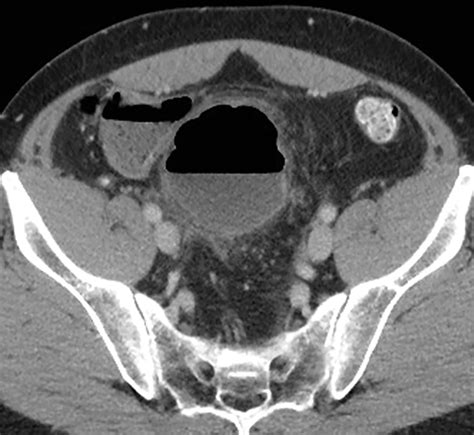

In most instances, individuals living with Sigmoid Colon Diverticulosis do not experience any discomfort at all. It is frequently diagnosed during a colonoscopy or a CT scan performed for other medical reasons. However, when symptoms do occur, they may include:

CT Scan Detailed cross-sectional imaging to identify inflammation.